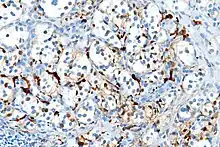

Micrograph of a carotid body tumor

S100 immunostain highlighting the sustentacular cells in a paraganglioma